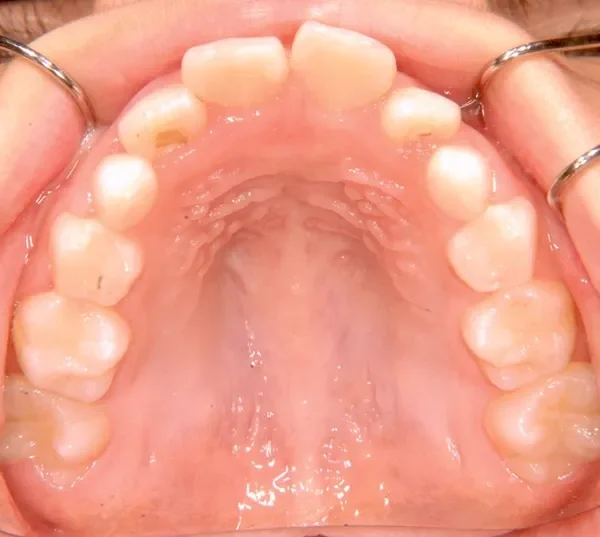

【子供の矯正(一期)】叢生・出っ歯・前歯がゆがんでいる・8才女児【H.M様】

初診時年齢 小学校3年生 (女性) 主訴 出っ歯・前歯がゆがんでいる

診断名 叢生・上顎前突 装置名

状態 永久歯が生える隙間がない(叢生)

ガタガタ・でこぼこに生えている(叢生)

出っ歯(口元が出ている/上顎前突)

出っ歯と前歯のゆがみを主訴に来院されました。